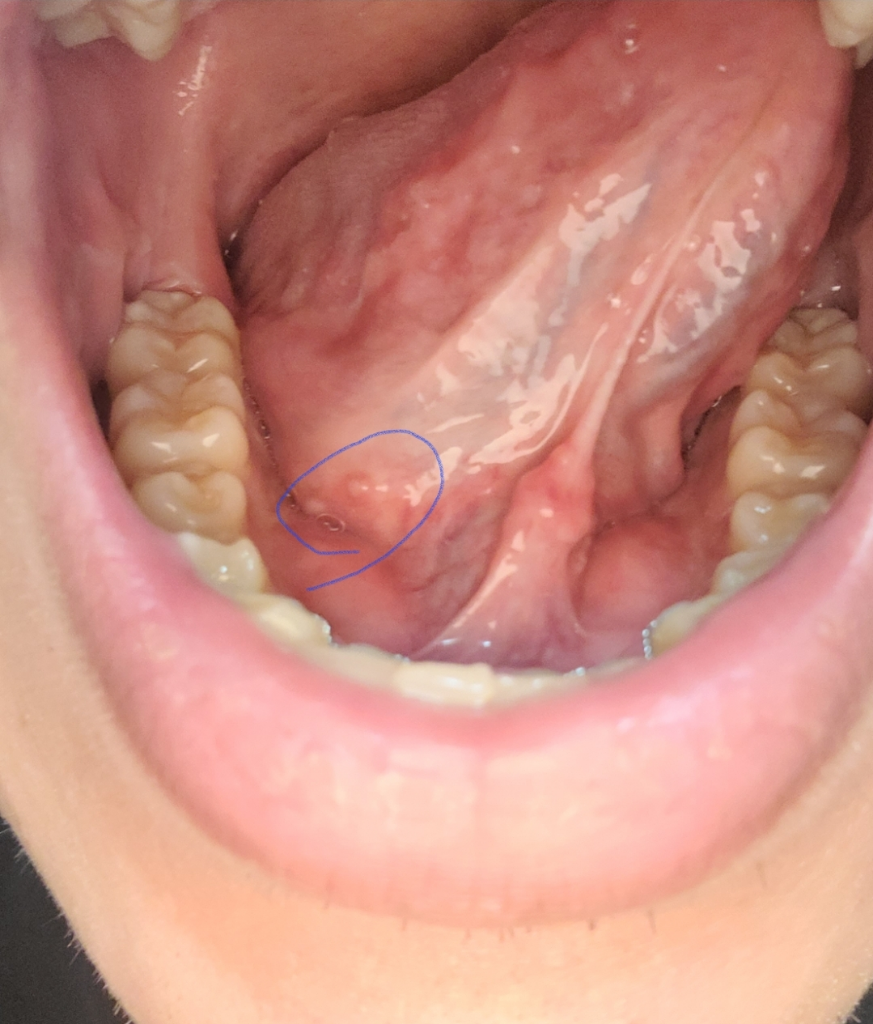

점액낭종 꼭 수술해야할까요??

1.저렇게 동그란 두개가 점액낭종이 맞을까요??

2. 지금 당장은 아니더라도 언젠간 수술을 꼭해야되는걸까요?? 그런거면 빨리하고싶어서요ㅠㅠ

• 1번 째 사진

점액 낭종으로 판단되지는 않습니다. 당연히 수술이 필요하지도 않을 것 같고, 그냥 놔두셔도 될 것 같습니다.